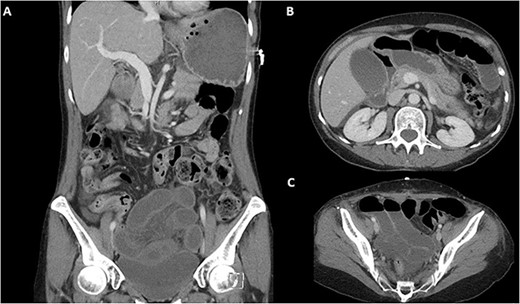

On examination she had generalized abdominal peritonism and distension with scant bowel sounds. She was otherwise hemodynamically stable and afebrile. Her pathology demonstrated a white cell count of 10.3 × 109/L and C-Reactive Protein of<1, and an elevated lactate of 2.1 mmol/L. A contrast computed tomography of her abdomen and pelvis was performed which demonstrated a high-grade closed-loop bowel obstruction in the pelvis with a transition point the in the left pelvic sidewall with ischemia but no necrosis of the loops at the time of the scan acquisition (Fig. 1). Small volume pelvic free fluid was also noted. The patient was taken directly to theatre for an emergency operation.

Pre-operative CT-abdomen pelvis of a closed loop bowel obstruction. (A) Coronal cross section. (B) Sagittal cross section of the abdomen. (C) Sagittal cross section of the pelvis.

We report a novel complication of malplacement of a V-Loc suture during RALSC resulting in a closed loop bowel obstruction (Fig. 1) and resultant ischaemic bowel (Fig. 2). Whilst barbed, absorbable sutures are widely utilized as they reduce suturing time and technical difficulty [6] they also carry a risk of bowel obstruction of 1/400 [7]. Most describe the adverse event occurring because of the entanglement of barbed wire tails between the intestinal mesentery or epiploic appendages [8]. With the lack of haptic feedback in robotic surgery, it is possible for surgeons to place a suture deeper than expected, which we hypothesize happened in this case.